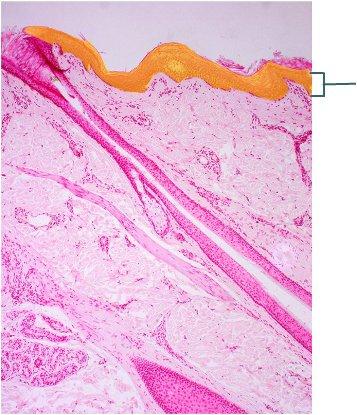

Which type of tissue is the highlighted region composed of?

stratum corneum

stratified squamous epithelium, keratinized

stratum spinosum

dermis

stratified squamous epithelium, keratinized

Which layer of the skin is highlighted?

papillary layer of dermis

reticular layer of dermis

hypodermis

epidermis

papillary layer of dermis